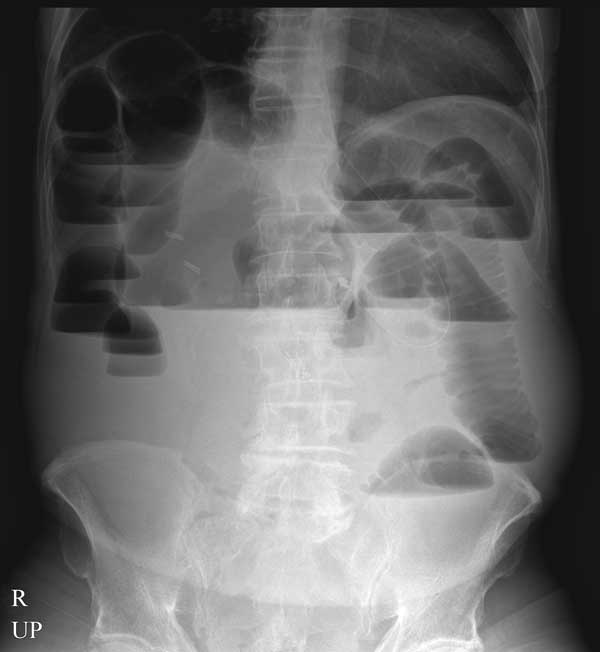

2) º¹ºÎ »çÁø ÇÑ Àå